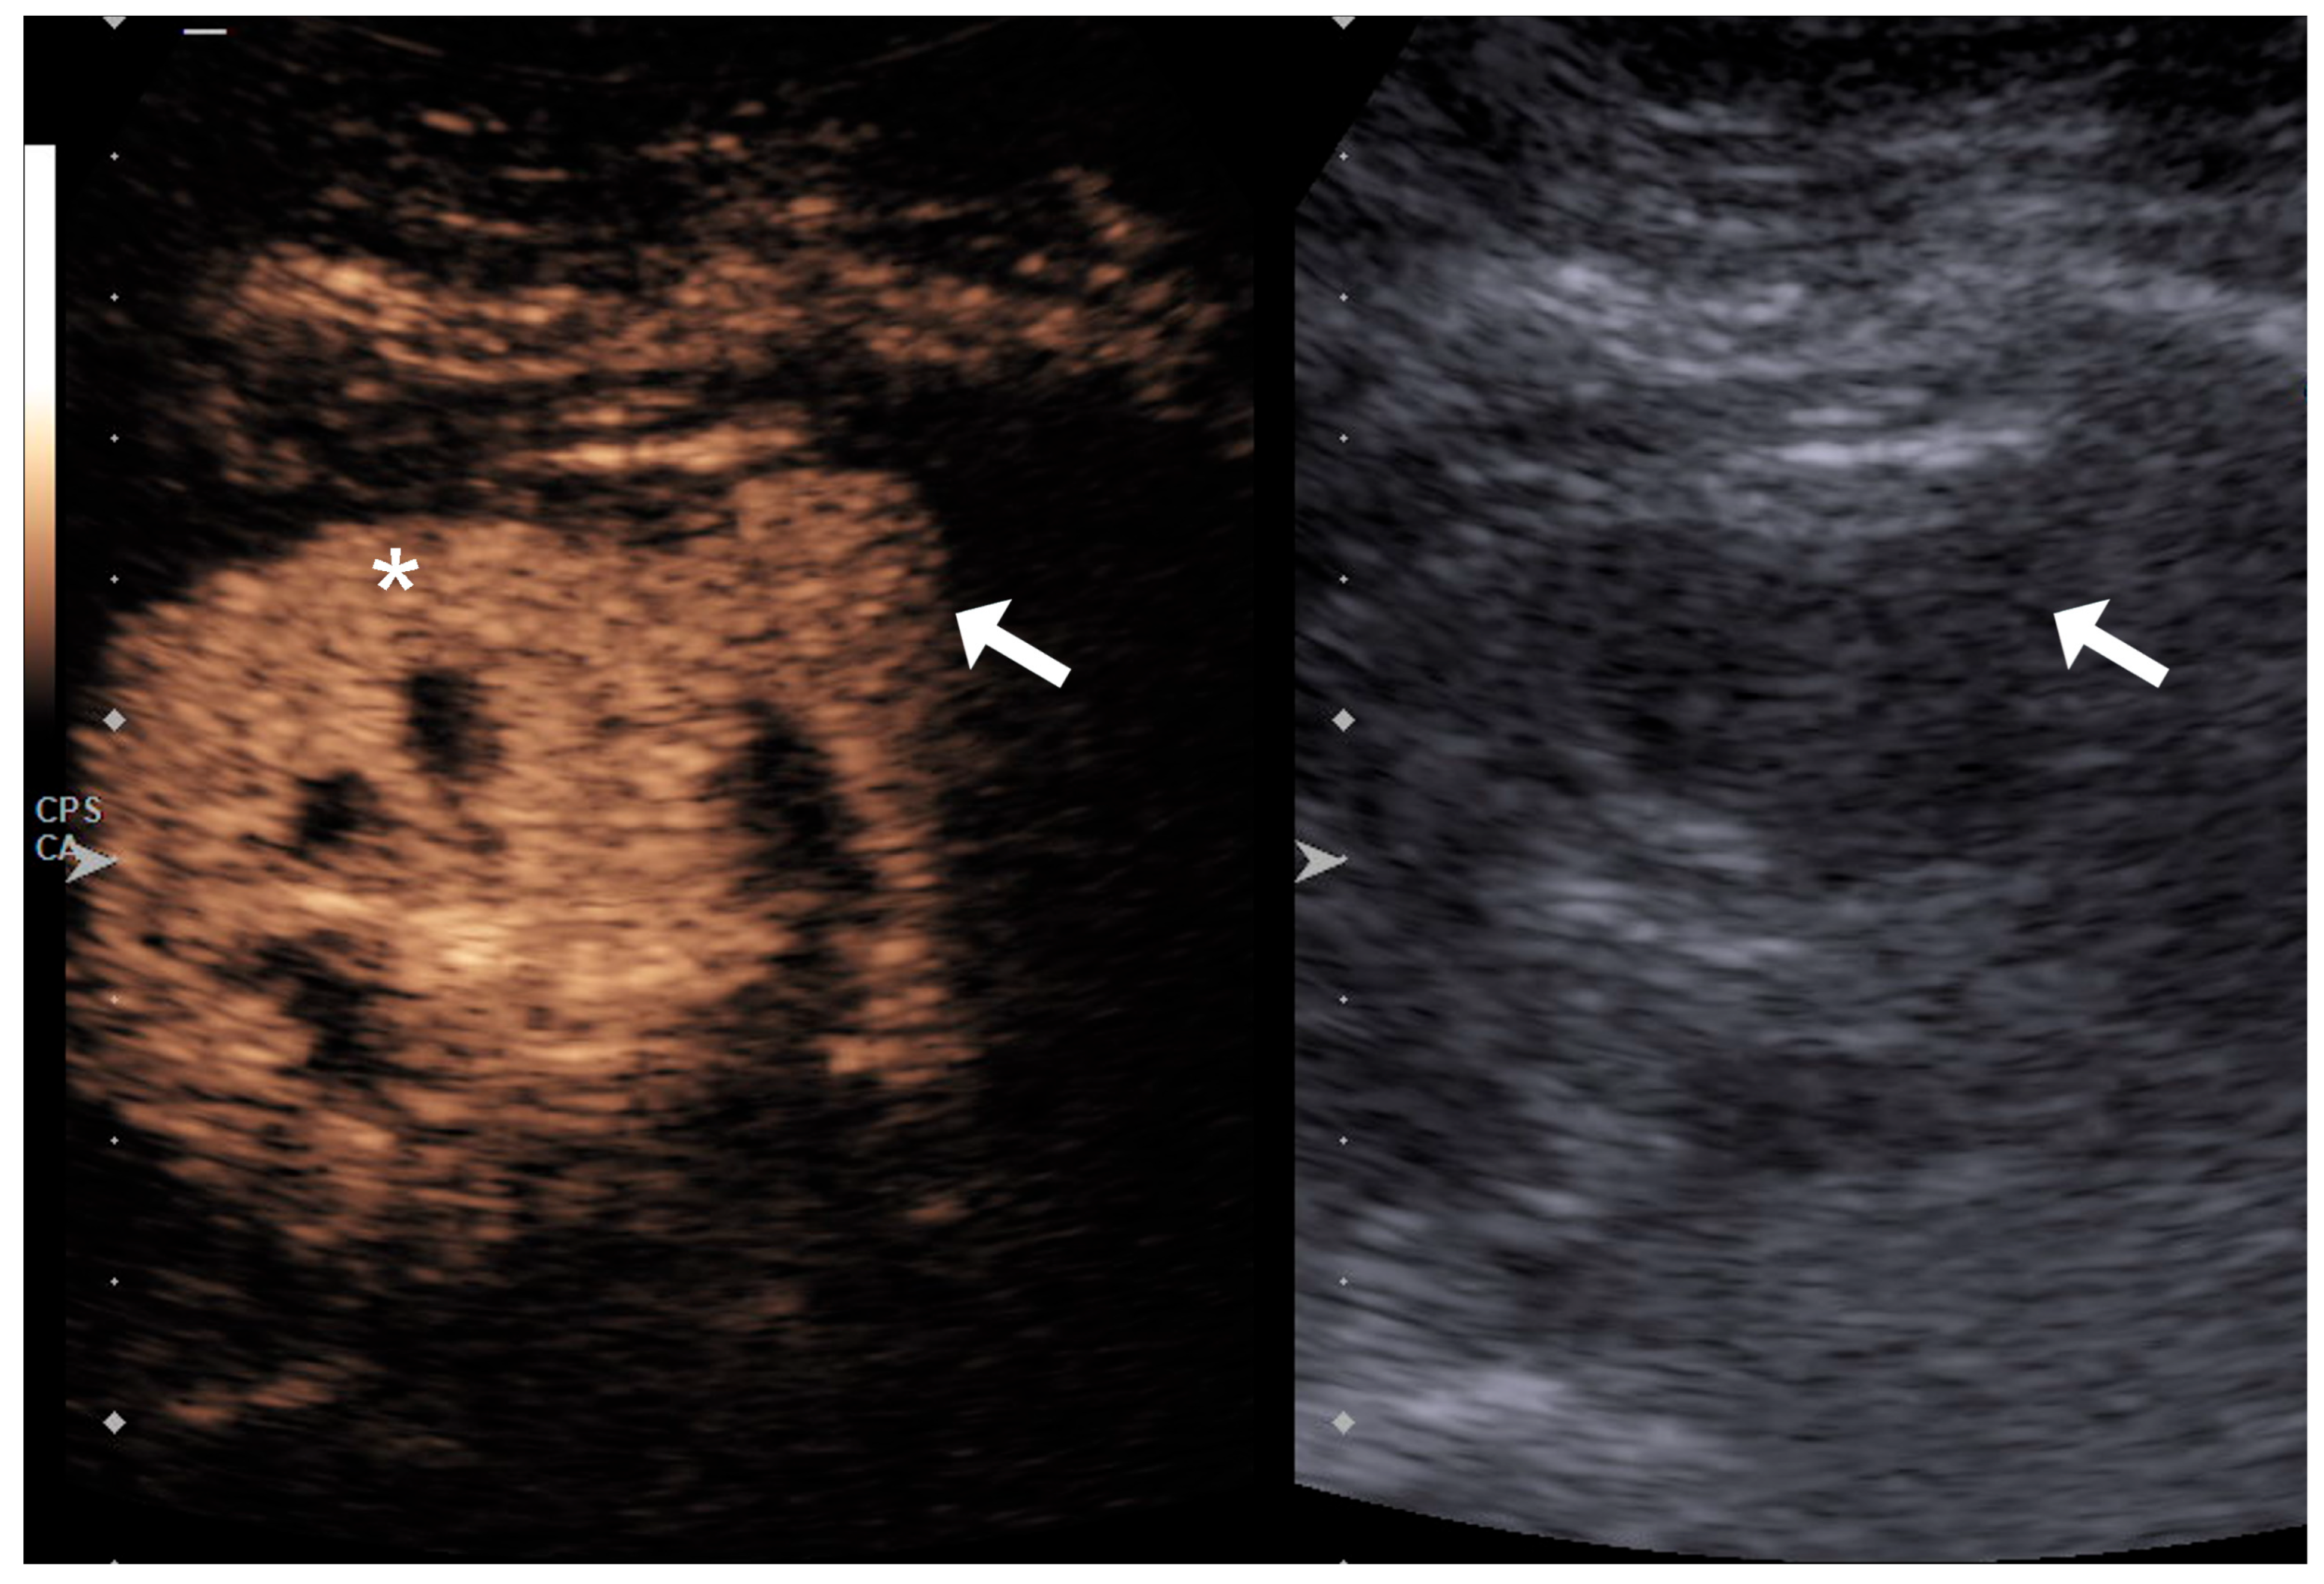

2.2. Image Acquisition and Analysis

4.1. Qualitative Evaluation